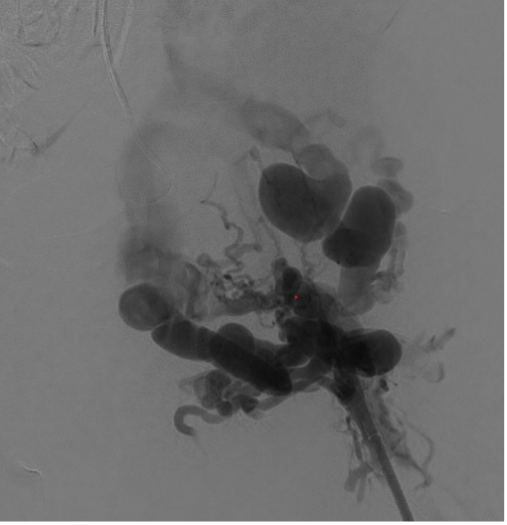

Venography was performed in multiple projections. The left groin exposure was utilized for ultrasound assessment of the target vessels. The cephalad channel appeared to parallel the left common femoral artery representing the anatomic location of the normal common femoral vein. The caudal channel was slightly deeper and posterior to the common femoral artery (Figures 3 and 4).

A 300-cm, .014-inch Fathom wire (Boston Scientific) was placed through the percutaneous needle and snared through each access sheath. With through-and-through access achieved, a direct femoral channel was established. Serial balloon angioplasty was performed with intermittent venography. Intravascular ultrasound (Philips) evaluation was also performed to document the channel. This showed a short segment of “uncovered” tract without visualization of the vein wall. At the same level, venography showed a small amount of extravasation of contrast, as expected. There continued to be filling of the large inguinal collateral veins, even after balloon dilation to 8 mm (Figure 7).